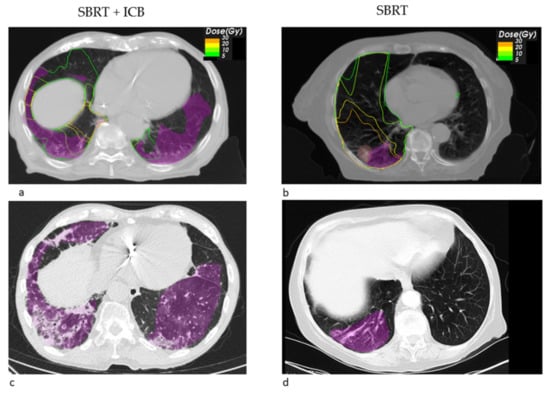

Figure 2. Transversal radiotherapy (RT) planning CT slices showing the sum EQD2 isodoses and pneumonitis contours (magenta) and GTV contours (light red) for a SBRT+ ICB case (a). This patient received simultaneous liver metastasis SBRT. The isodoses of the original treatment plan show a negligible lung dose (b). Figure (c) shows an exemplary sagittal slice from the follow-up CT showing the bilateral pneumonitis and its contours (magenta).

Looking at the dosimetric results in more detail, we observed a trend towards a decreased fraction of the pneumonitis volume receiving a high dose of EQD2 > 20 Gy SBRT + ICB (22.26% vs. 71.14%, p = 0.549), whereas the mean low dose fraction with EQD2 < 10 Gy was numerically larger (39.02% vs. 26.99%). Figure 1 shows the pneumonitis extensions and EQD isodoses for two exemplary cases from both groups. For the depicted SBRT + ICB case, the pneumonitis affects both lungs with a rather small single-sided GTV distant from the resulting radiological changes. For another patient, who received SBRT with 45 Gy in 3 fractions to a small left-sided tumor, we also found bilateral extent of pneumonitis, as shown in Figure 2. This patient received additional SBRT for liver metastasis at the same time with the same dose fractionation regime; however, the extent of pneumonitis does not correlate with the dose distribution. For dosimetric analysis, we used sum doses to prevent overestimation of the effect attributed to the lung SBRT. A third patient also showed the bilateral extent of pneumonitis. This patient received hypofractionated, contralateral mediastinal RT with 45 Gy in 15 fractions a month prior to SBRT. Since the extent of the pneumonitis volume in the contralateral right lung is more likely caused by the irradiation of the right side, we considered only the pneumonitis contour from the left SBRT side for analysis. However, to not overestimate the dosimetric effect of SBRT alone, we used the sum EQD2, as shown in Figure 3a, for dosimetric evaluation as well.